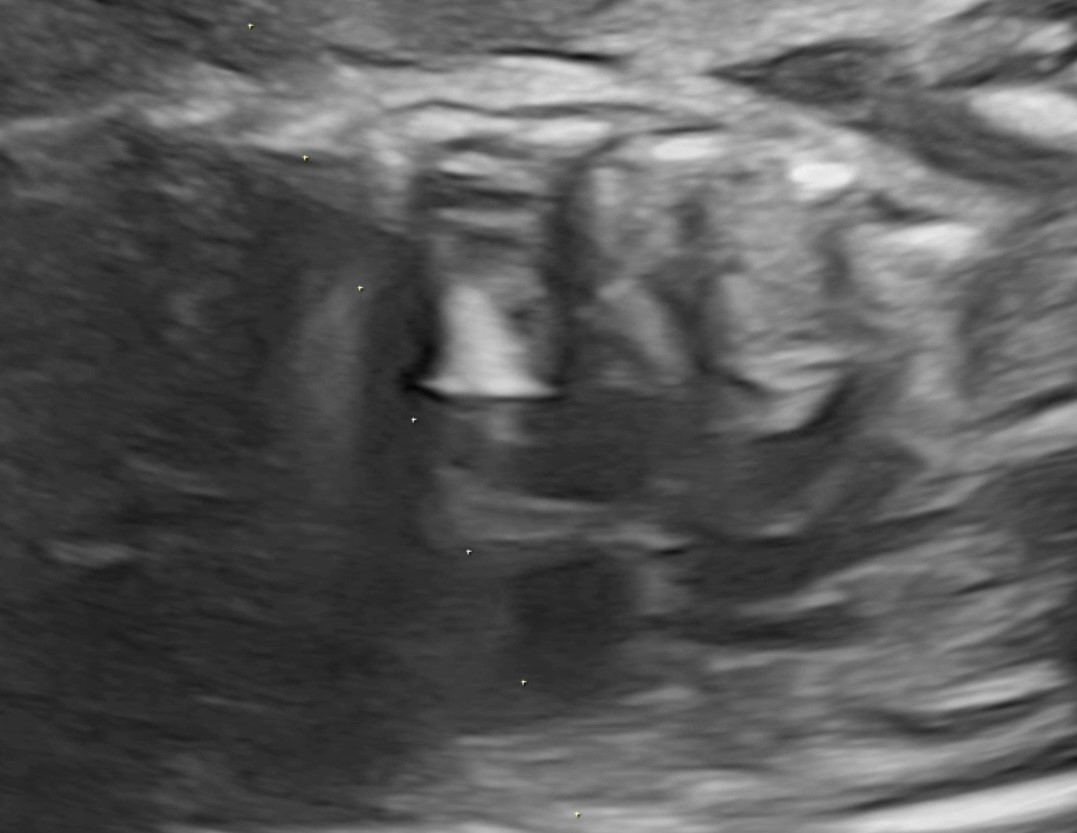

3 b. после выполненной вальвулопластики клапана аорты и извлечения баллона с иглой

По данным ультразвукового исследования после выполненной вальвулопластики клапана аорты и извлечения баллона с иглой отмечается увеличение эффективного отверстия клапана аорты и отсутствие жидкости в полости перикарда.

Через 12 часов после операции было проведено ультразвуковое исследование сердца плода. Фракция выброса ЛЖ увеличилась до 24 %, диаметр эффективного отверстия АК составил 2,9 мм. Максимальный градиент на АК возрос до 21 mm Hg, митральная регургитация уменьшилась с тотальной до 2 степени. Жидкости в полости перикарда обнаружено не было.